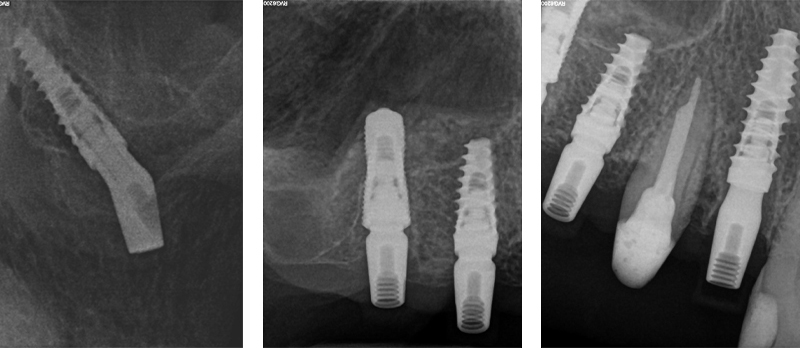

La finalizzazione del caso avveniva con protesi in metallo-ceramica passivata su cappe conometriche in bocca (Figs. 24, 25, 26, 27, 28, 29, 30, 31, 32) e radiografie finali ad un anno dal carico (Figs. 33, 34).

Figs. 32, 33, 34 - Radiografie finali impianti 17, 15, 14 ad un anno dal carico con guarigione del rialzo di seno trans-crestale del 15, impianto pterigoideo 17 e Socket Shield 12